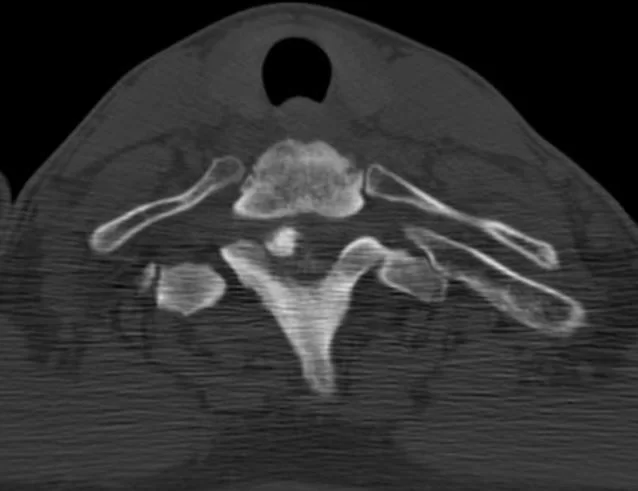

Ο απεικονιστικός έλεγχος έλεγχος με μαγνητική και αξονική τομογραφία της αυχενικής μοίρας της σπονδυλικής στήλης ανέδειξε χωροκατακτητική εξεργασία στο ύψος του Θ1-Θ2 σπονδύλου

Προεγχειρητικός Απεικονιστικός Έλεγχος (εγκάρσιες εικόνες)